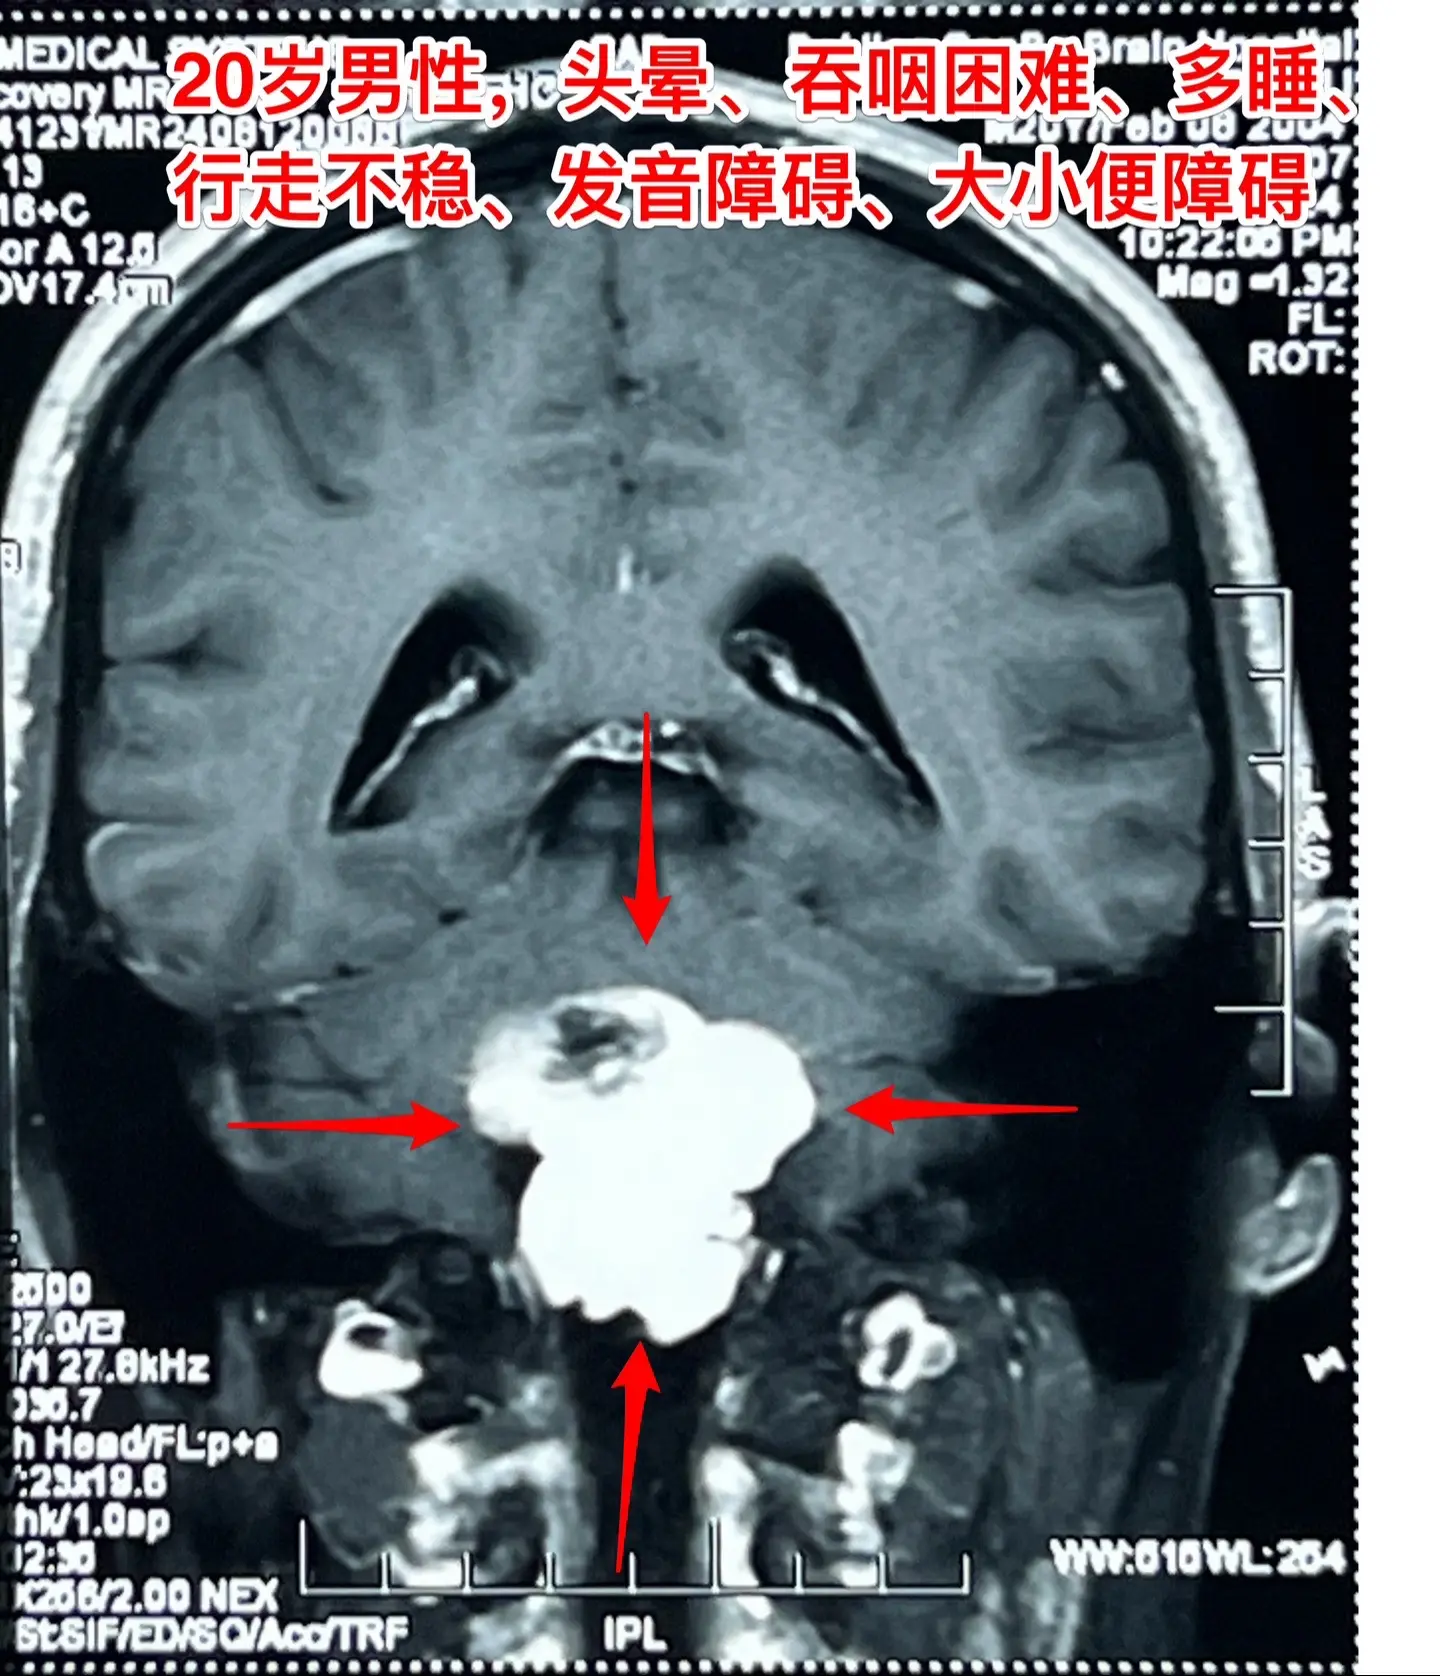

头晕、吞咽困难、行走不稳、大小便障碍。20岁漳州的小伙子,2个月前出现...

2024-08-16 15:27